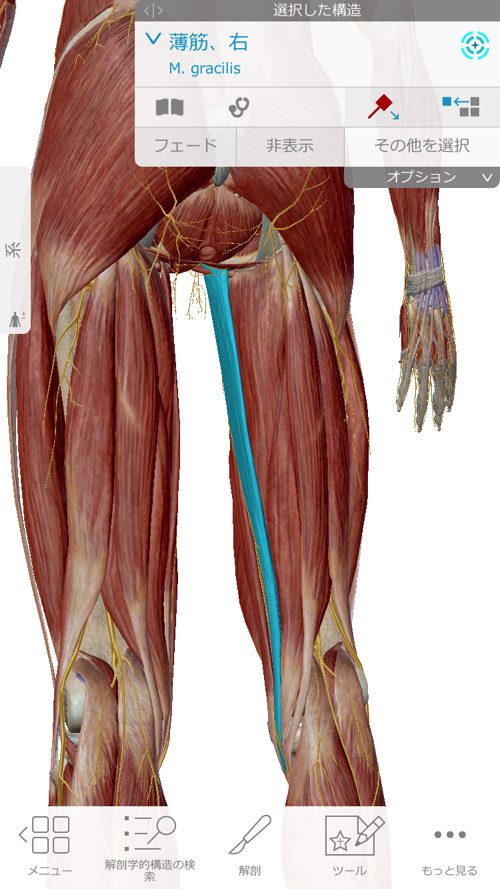

今回のぎっくり腰で特にしっかりと施術した場所はここ

それから薄筋や、大内転筋

これらの筋肉や腱の硬直を1つ1つ解いて

ズレやヨジレを丁寧に戻していく施術をさせて頂きました。